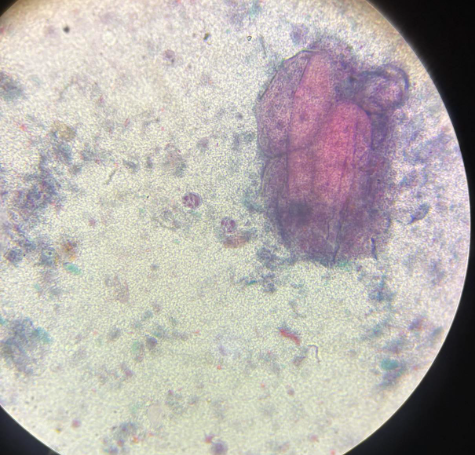

fasciola hepatica postać dojrzała